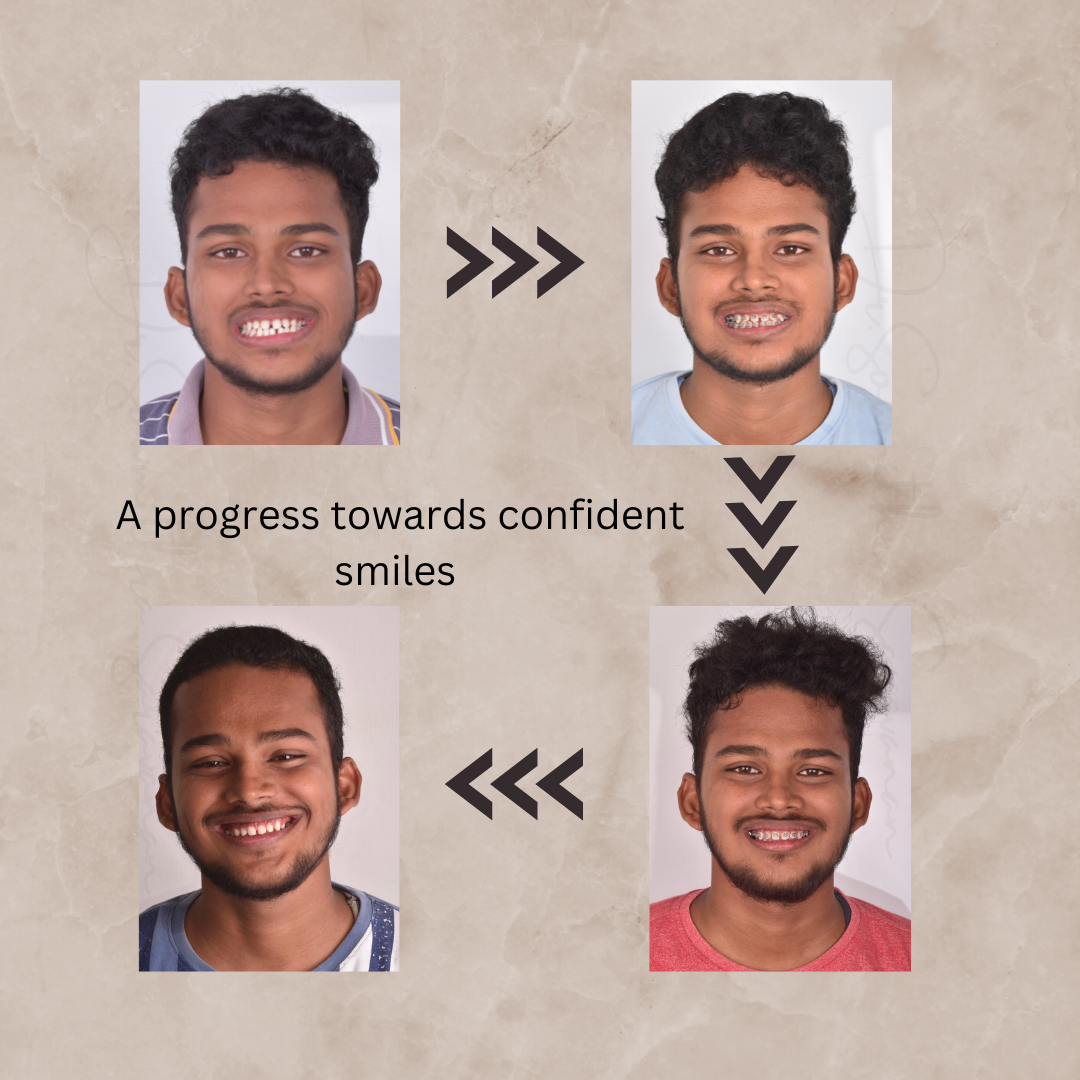

BRINGING OUT CONFIDENT SMILES- AN ORTHODONTIC SMILE REVEAL

BRINGING OUT CONFIDENT SMILES- AN ORTHODONTIC SMILE REVEAL